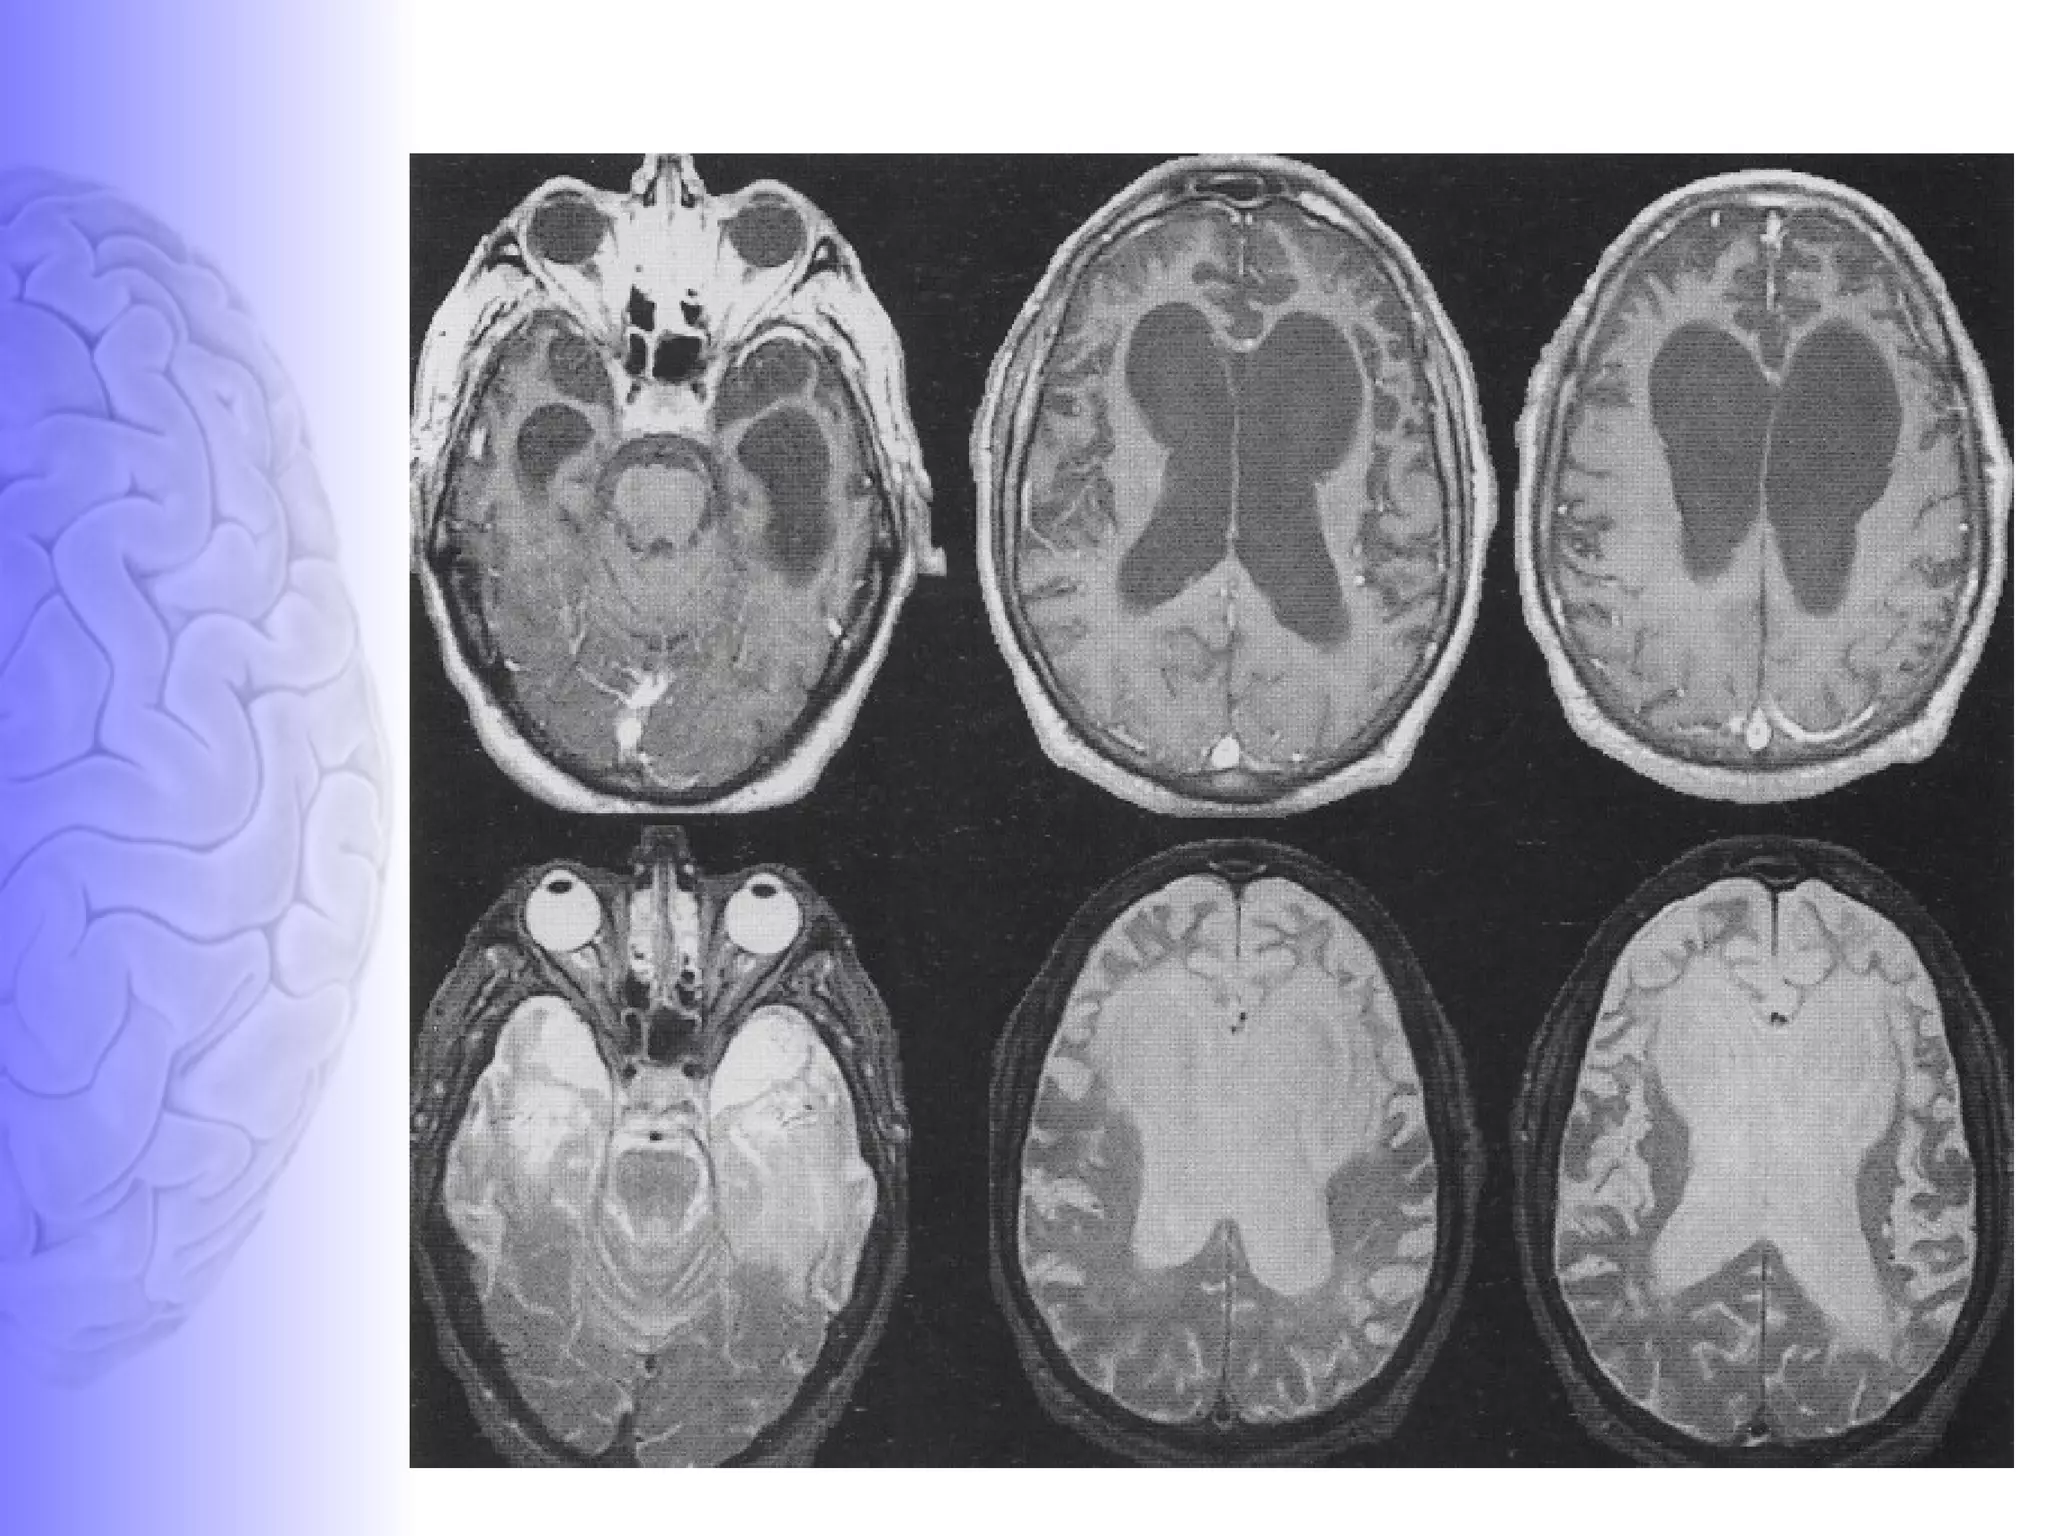

Basics - MRI T1 weighted imaging- Basis is the longitudinal relaxation (spin lattice relaxation) T1  image created typically by using short TE and TR times (TE –echo time ::TR – repetition time ) Fat (larger longitudinal and transverse magnetization) - Bright on a T1  Water (less longitudinal magnetization)-Dark on T1

Basics - MRI T2 weighted imaging- Basis is the transverse relaxation (spin spin relaxation) T2 created typically by using longer TE and TR times. Fat (larger longitudinal) - Dark on a T2  Water (less longitudinal magnetization)-White on T2

T1- weighted MR  T2- weighted MR  CT Scan